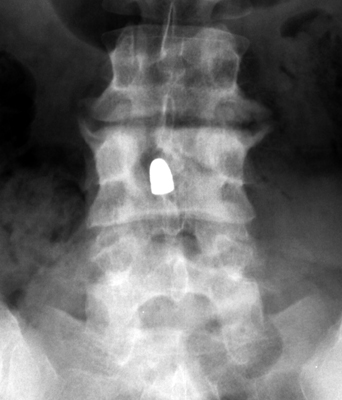

Two sets of frontal and lateral radiographs, separated only by time, which reveal the "tumbling bullet sign"--which is simply a bullet which changes its location and orientation within a solitary bone cyst. This sign serves two purposes. It is documentation of the evolution of a solitary bone cyst as a corollary of trauma, and reveals the free movement of the foreign body within the confines of the lesion establishing its cystic rather than solid nature. It is similar to the fallen fragment sign.

- Click on the image for a larger versionA - Click on the image for a larger versionB - Click on the image for a larger versionC - Click on the image for a larger versionD